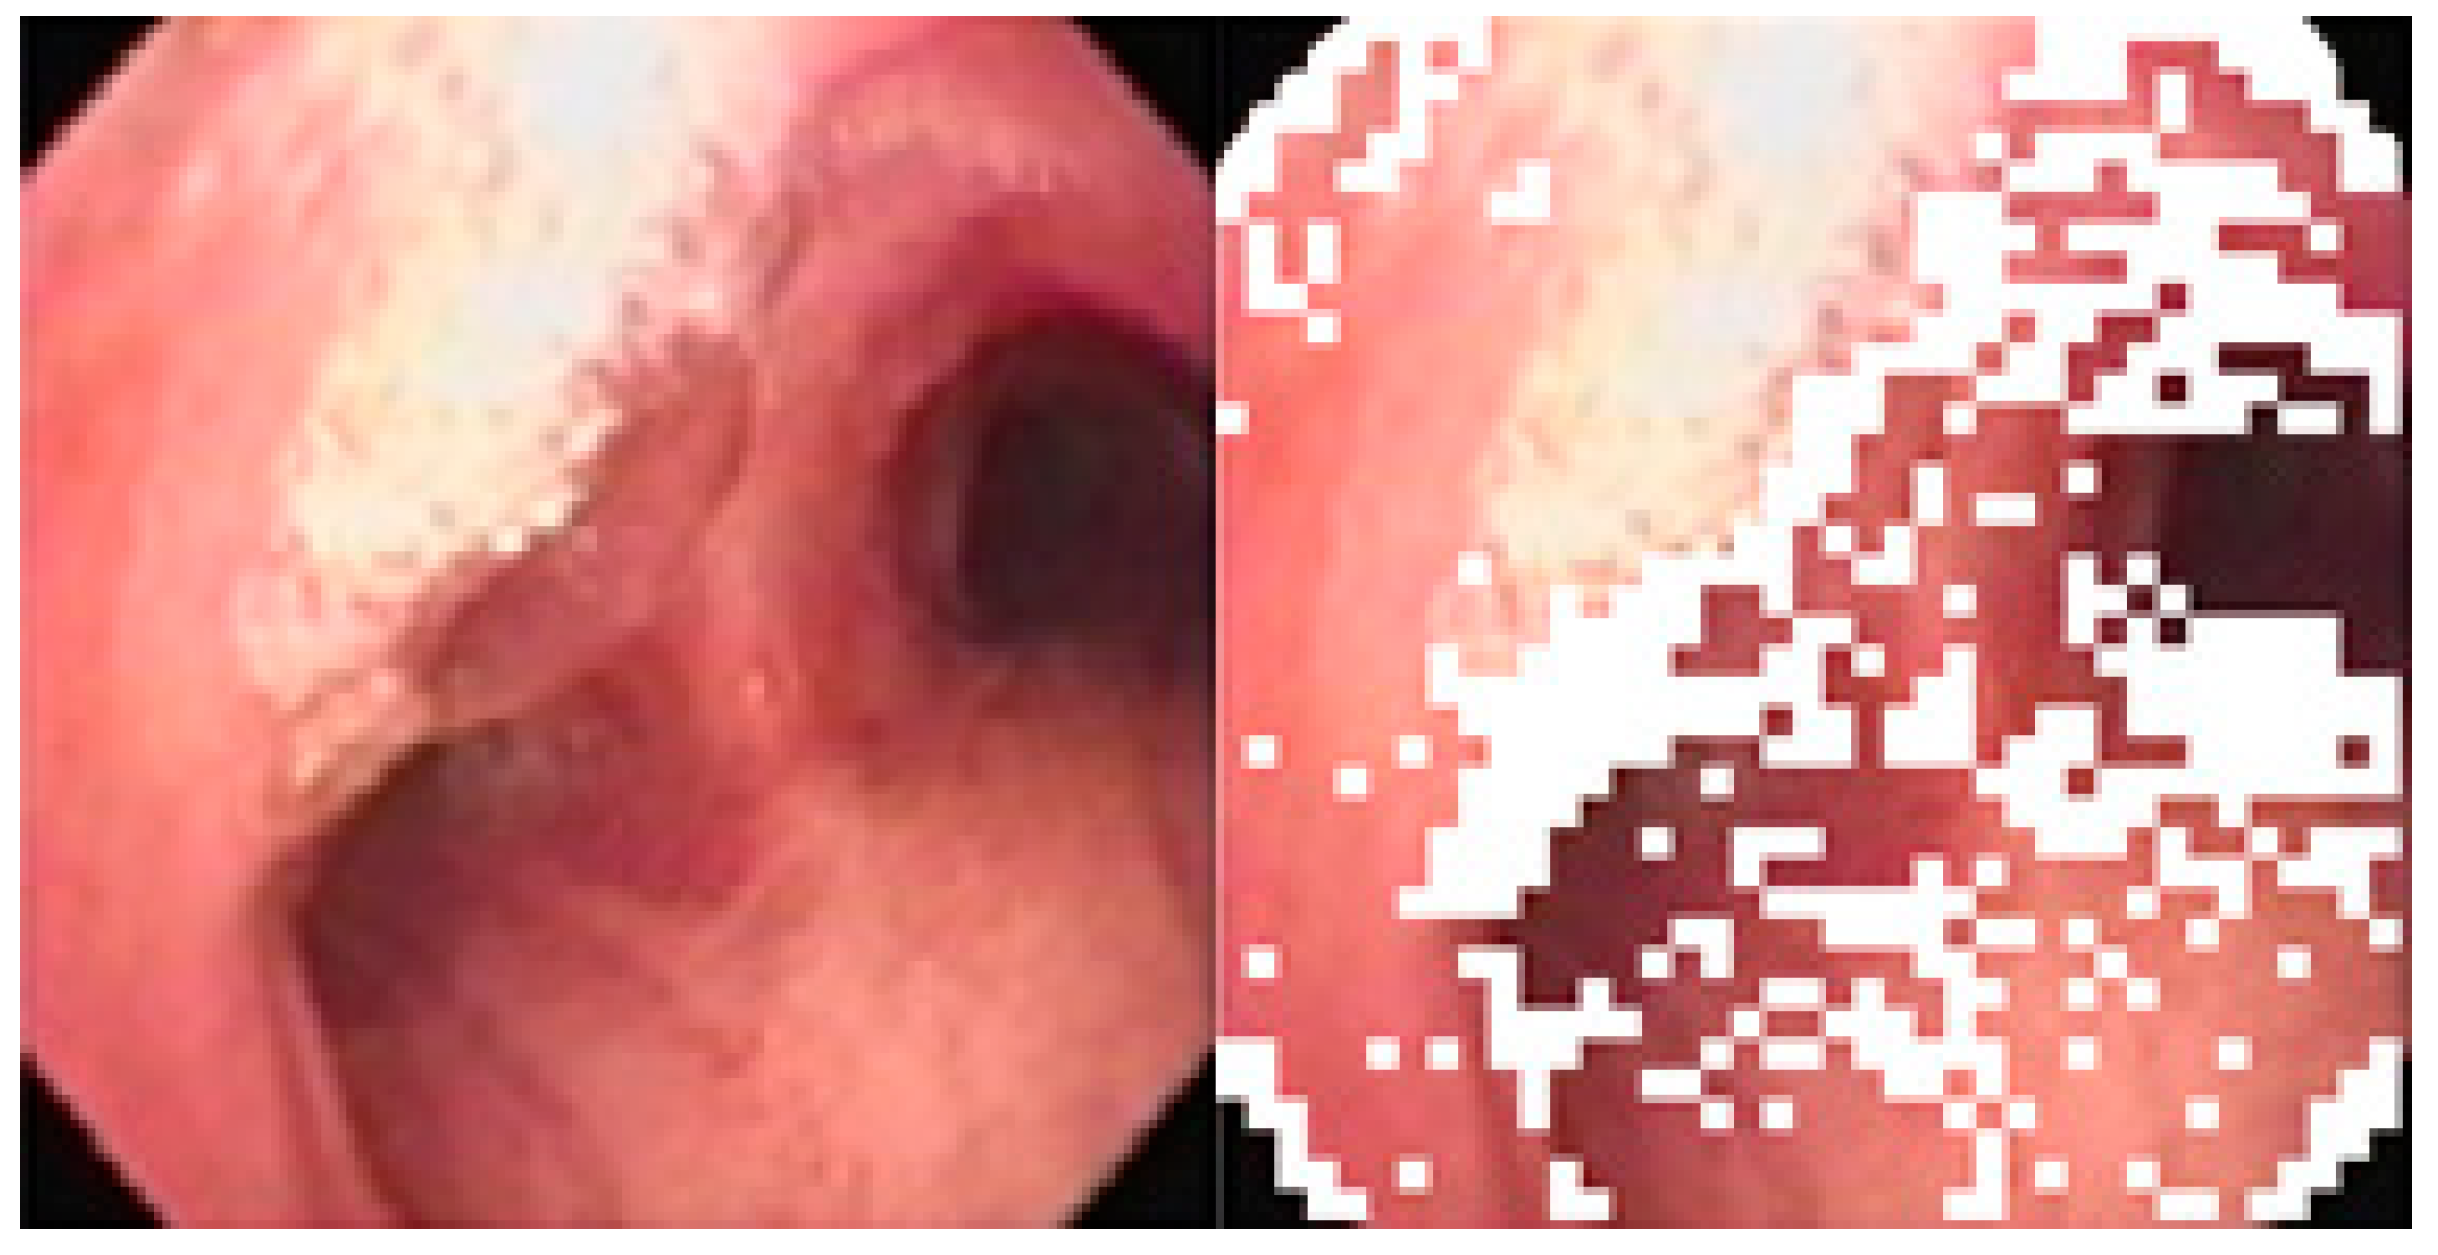

However, areas of high reflectance can cause error during the matching, and so they are removed from consideration prior to matching, as shown below in Figure 9.

Figure 9.

Removing areas of high reflectance from matching: (a) original (b) removed.

The image subblocks, each of 40 × 40 pixels in size, with high reflectance are determined using an ANFIS-system using the mean saturation and mean value of an image subblock as the input, and using the COG (center-of-gravity) for defuzzification. Figure 10 below shows the differences between using a threshold vs. ANFIS-based results in determining areas of high reflectance on two random images. It is obvious that ANFIS is more accurate at determining areas of high reflectance and thus preserves more pixels for consideration.

Figure 10.

Areas of high reflectance: (a) original image, (b) threshold-based correction, (c) ANFIS-based correction.